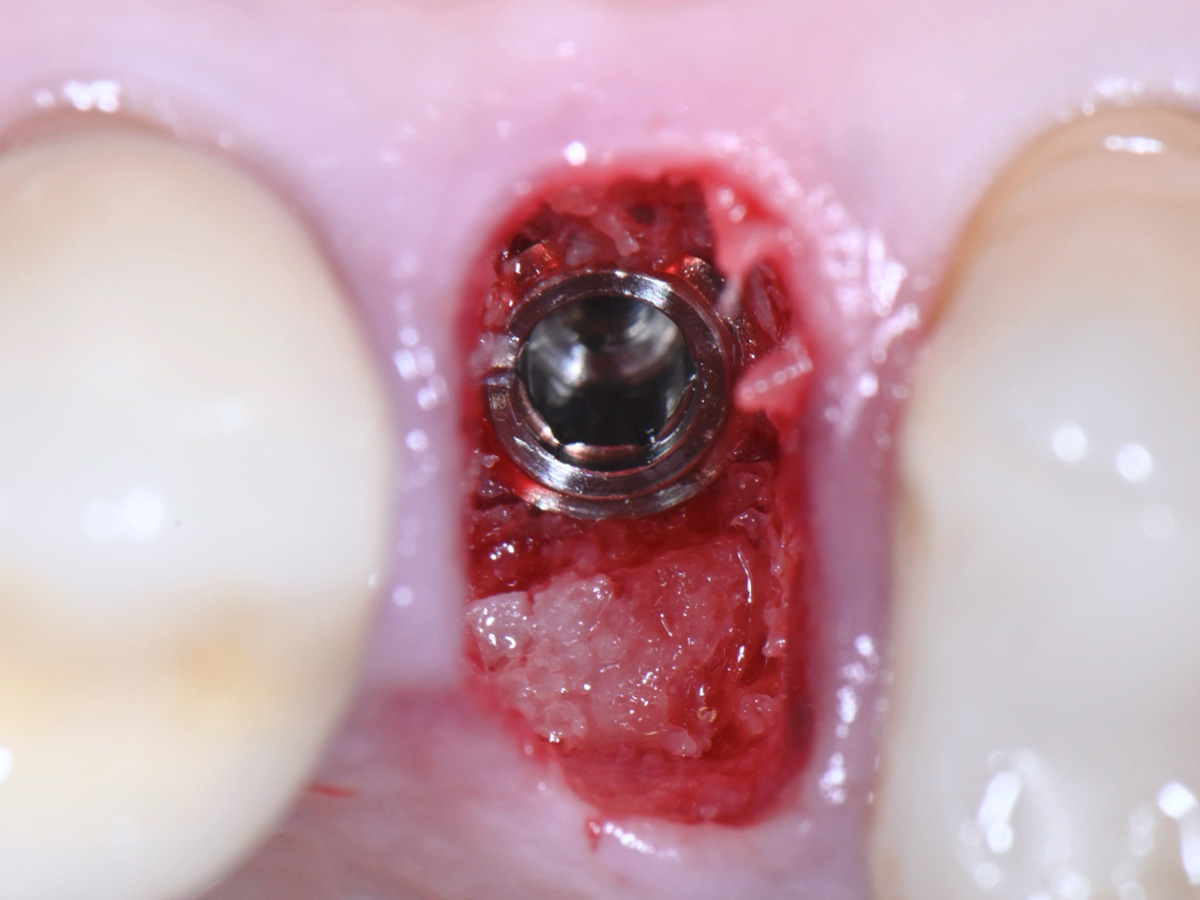

Abbildung 7

Sondierung der Extraktionsalveole mit einer Kugelsonde